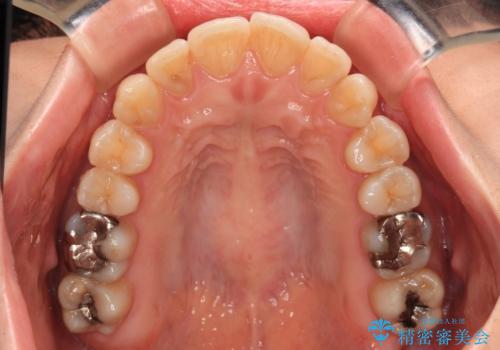

矯正治療後には奥歯の銀歯やむし歯をセラミックやゴールドにて治療を行い、大変整った口腔環境へと改善さ。れました